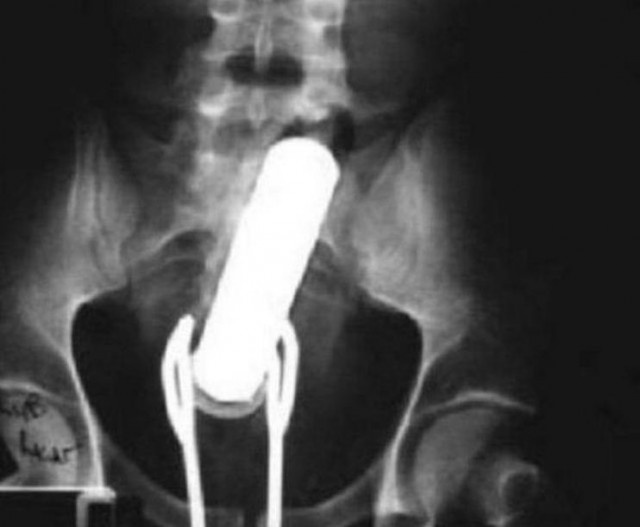

・取り出そうとトングを入れたらトングまで詰まったそうです